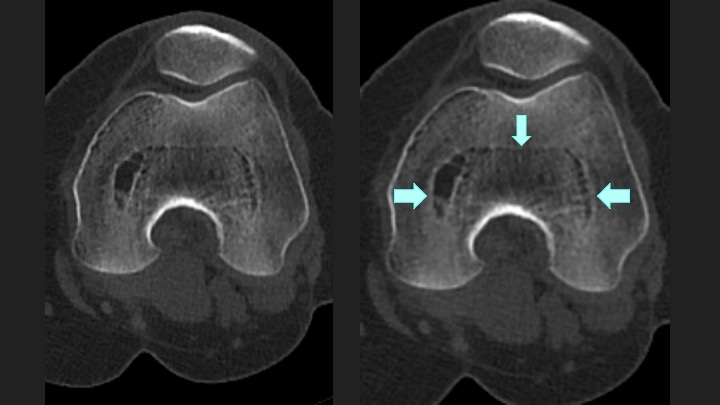

This is completely incidental in someone for Hip MakoPlasty pre op CT….no such changes at the hip. The Sag is most striking.

I’ve put arrows and masked what I’m seeing so you can hallucinate along with me.